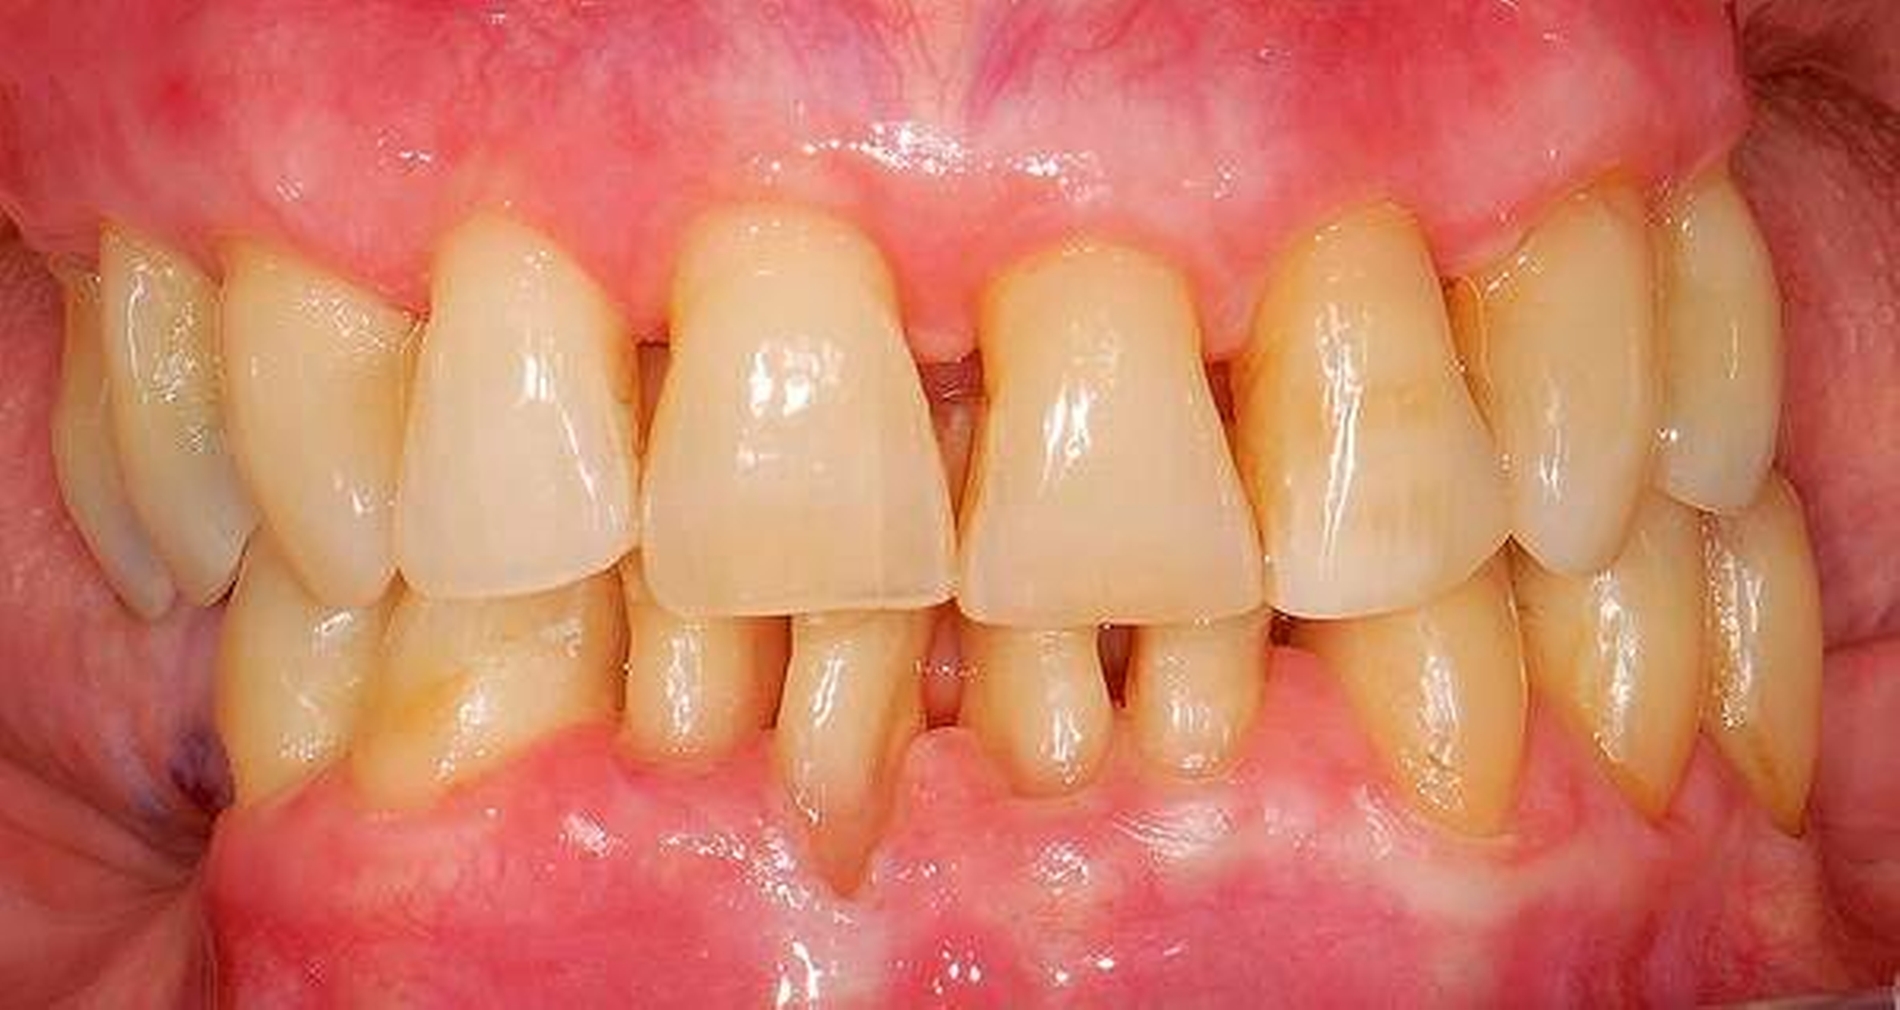

In der Zahnmedizin ist ein Dogma weit verbreitet: „Jede Lücke muss rasch geschlossen werden.“ Tatsächlich gibt es jedoch viele Situationen, in denen es ohne relevante funktionelle und ästhetische Einbußen vertretbar erscheint, eine Lücke zu belassen und regelmäßig zu beobachten (Monitoring). Derzeit erfolgt die Entscheidung „Lücke belassen versus Lücke schließen“ oftmals subjektiv. Sie ist zuweilen weniger von den Patientenvariablen abhängig als von den Schwerpunkten der betreuenden Zahnärzte (Abbildung 4) [Listl et al., 2016]. Ein fachlich fundiertes Vorgehen, das eine Entscheidung unter einer Nutzen-Risiko-Abwägung trifft und ein Monitoring in die Überlegungen einbezieht, kann ebenfalls in die Kategorie der frugalen Interventionen eingeordnet werden. Gleiches gilt für ein Vorgehen im Sinne des Prinzips der verkürzten Zahnreihe, das inzwischen wissenschaftlich gut evaluiert ist [Walter, 2016] und zu dessen Realisierung auch konservierende Maßnahmen beitragen können (Abbildung 5).

Abbildung 4: Überwachtes Monitoring (Belassen und Beobachten) von Zahnlücken